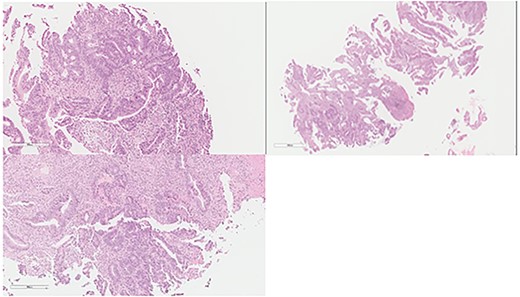

The patient was clinically and vitally stable post operation and was recovering well upon discharge. Pathology revealed no residual tumor, extensive necrosis and calcification with no viable cancer cells with a complete response and a score of 0. Moreover, the sigmoid colon specimen revealed no viable cancer cells, complete response, a score of 0 and nine lymph nodes were found to be negative to malignancy (0/9) (Fig. 4).

Colon: status of post NAC with complete response. Mucosal ulcer, fibrosis, calcification and histolytic collection with no tumor cells.